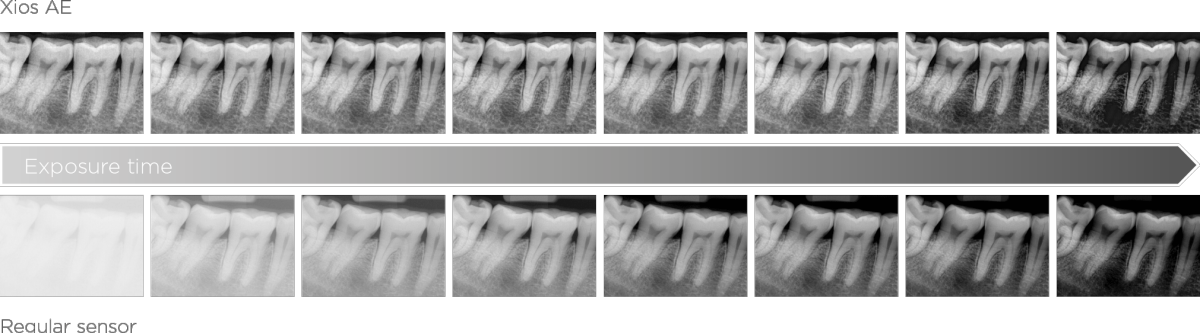

More Details to Maximize Your Diagnostic Potential

Xios AE sensors support a high clinical performance level with superior image quality and advanced filtering enhancements to highlight relevant anatomical structures and facilitate an accurate and detailed diagnosis. Low-noise images, improved visibility of details, and dedicated filtering in indications such as endodontic cases or tooth decay, provide a relevant advantage in diagnostic certainty and help aid true confidence in the treatment assessment. When combined with smart connectivity between the hardware and Sidexis 4 software, you get the perfect partner for any practice.